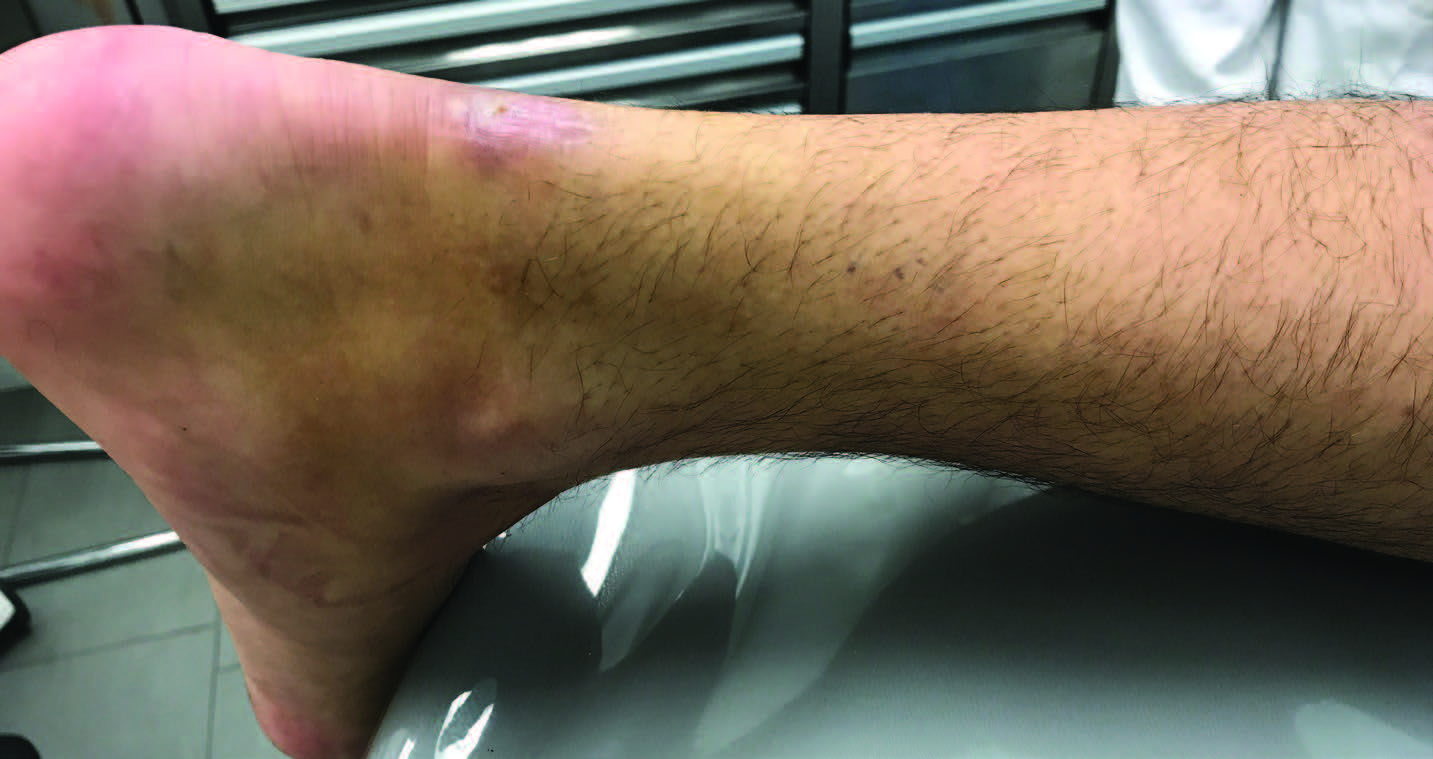

Achilles tendon injuries often cause pain, stiffness, and swelling in the back of your leg near your heel.

Achilles tendon injury prevention. For people with more severe injuries, a doctor may recommend surgery. Treatment treatment for a ruptured achilles tendon often depends on your age, activity level and the severity of your injury.

An achilles tendon rupture may need surgical repair within days of the injury. First, do this exercise with your knee straight. To decrease pain or swelling, apply an ice pack to the tendon for about 15 minutes.

We show you only the best treatments for your condition and symptoms—all vetted by our medical team. She will make the correct diagnosis and develop an individualized treatment plan for your specific injury. Warmth around the heel or along the tendon difficulty standing on your toes thickening of the achilles tendon causes of achilles tendinitis